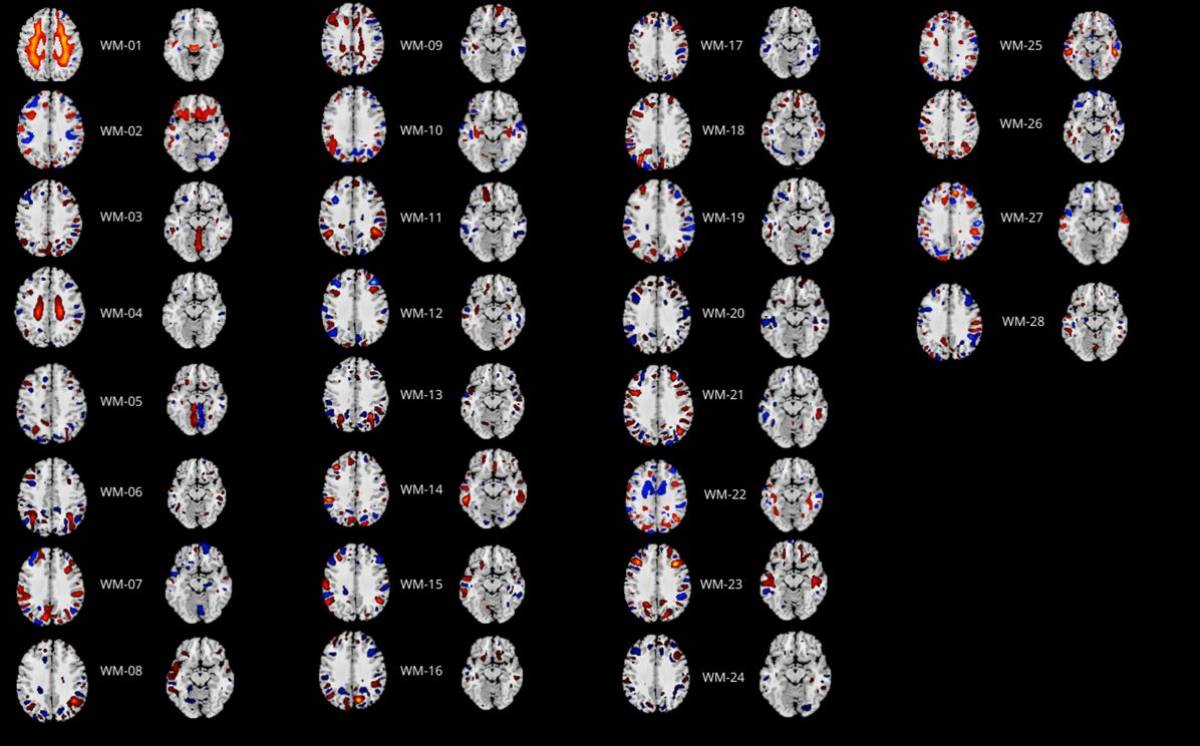

En este nuevo estudio se llevaron a cabo análisis de imágenes de la materia gris y blanca del cerebro de 30 individuos de Tenerife diagnosticados con TPOC, así como un número similar de participantes control. Para llevar a cabo este estudio, se utilizó una técnica de aprendizaje automático denominada análisis de componentes independientes en paralelo, o Parallel ICA. Esta herramienta permite analizar de forma conjunta distintos tipos de imágenes cerebrales, en este caso de materia gris y blanca, y detectar las redes cerebrales amplias activas en estado de reposo, identificando patrones y reduciendo la complejidad de la información.

De este modo, se pudo comprobar que varias regiones cerebrales vinculadas a la red neuronal por defecto (RND), presentaban alteraciones en personas aquejadas de este trastorno. En concreto, los resultados indicaron que dos redes de materia gris (GM-05 y GM-23), así como una red de materia blanca (WM-25) difieren entre ambos grupos.